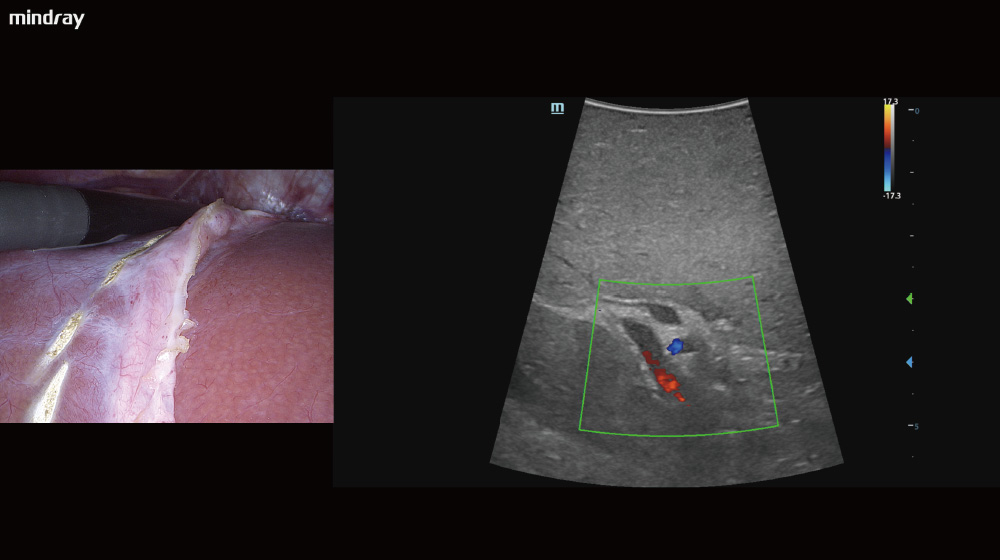

Multimodal Image Fusion

The real-time display of ultrasound images on the endoscope screen helps the surgeon localize the hidden lesion. Simultaneous recording of ultrasound and endoscope images on the same screen makes teaching and sharing more efficient.